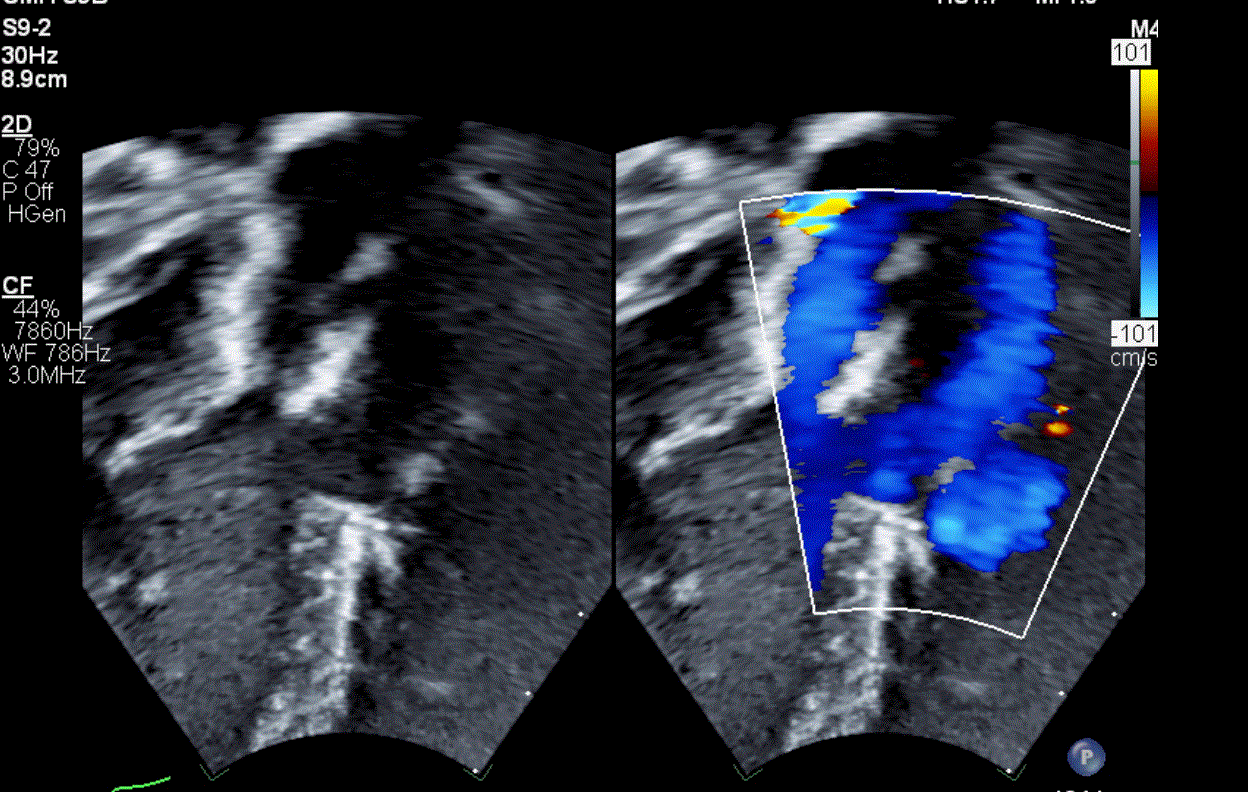

What is Wrong?

Too small, Adjust scale Difference in the two / 27%